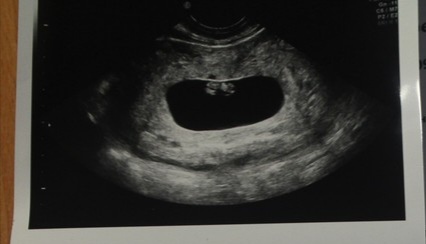

Ну что, кто спец по методу рамзи 😀

Счас дам 3 фото, узи во всех случаях вагинальное, срок по М 7-8 недель :)

Смотрят место прикрепления - если по правой стороне, то девочка, если по левой, то мальчик.

извините, может и мне подскажите, это у подружки)

Оо, вот тут сложно определить, по мне так прикрепление ровно по центру сверху. Вообще не вижу смещение ни в лево ни в право. Малыш- загадка))

Вообщем типа от места прекрерления ребёнка, можно с большей вероятностью угадать пол ребёнка :) но я не понимаю как смотреть, от чего зависит и тд 😂 там вроде если узи вагинальное, то надо как то зеркально смотреть, вообщем мне не понять :)